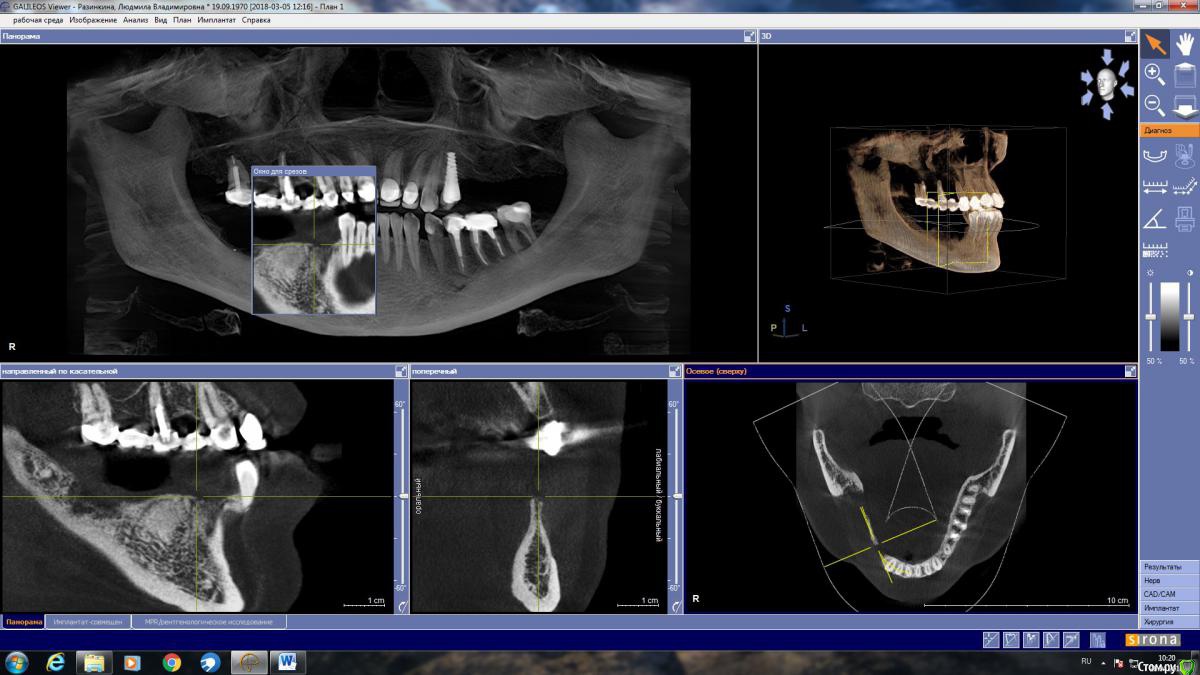

LjudmilaRaz Опубликовано 27 апреля, 2018 Поделиться Опубликовано 27 апреля, 2018 Здравствуйте! Напишите, пожалуйста, своё мнение. В первую очередь планирую имплантацию снизу справа!Обращалась на консультацию к трем врачам. Первый имплантолог предложил нарастить кость и установить четыре импланта. Врач работает только с имплантами одной фирмы (немецкие). Смутило, что полгода назад вариант был совершенно другой и еще то, что очень дорого.Второй предлагает нарастить кость и установить имплант Астра на месте удаленной в декабре четверки со смещением ближе к месту пятерки, и имплант Анкилоз на месте семерки со смещением к шестерке. То есть, накрыв мостом, получится не четыре, а три зуба.Такой же вариант, но с южно-корейскими имплантами (работаю только с ними), предложил третий имплантолог. Это относится к случаю, когда если двое говорят разное, то стоит послушать третьего ? Ссылка на комментарий

LjudmilaRaz Опубликовано 10 мая, 2018 Автор Поделиться Опубликовано 10 мая, 2018 Здравствуйте!С врачом определилась, опытный ЧЛХ стоматолог-имплантолог, еще раз сходила на консультацию. Он считает, что в моем случае более щадяще будет использование костной пластины животного происхождения, которая, становясь после определенных манипуляций пластичной, обогнет с обеих сторон в районе 4 и 5 снизу справа, где в дальнейшем планируется установка двух имплантов (плюс еще один в районе 7-ки - в итоге 3 штуки). По его мнению, ранее им планируемое расщепление в моём случае может стать по факту невозможным, из-за анатомически неблагоприятной ситуации - мало кости. Есть место (практически 2 мм) где при рассечении кость может "съесться" инструментом.Только в моей голове всё сложилось, и тут новый виток. Что думаете про такой способ костной пластики для моего случая. Ссылка на комментарий